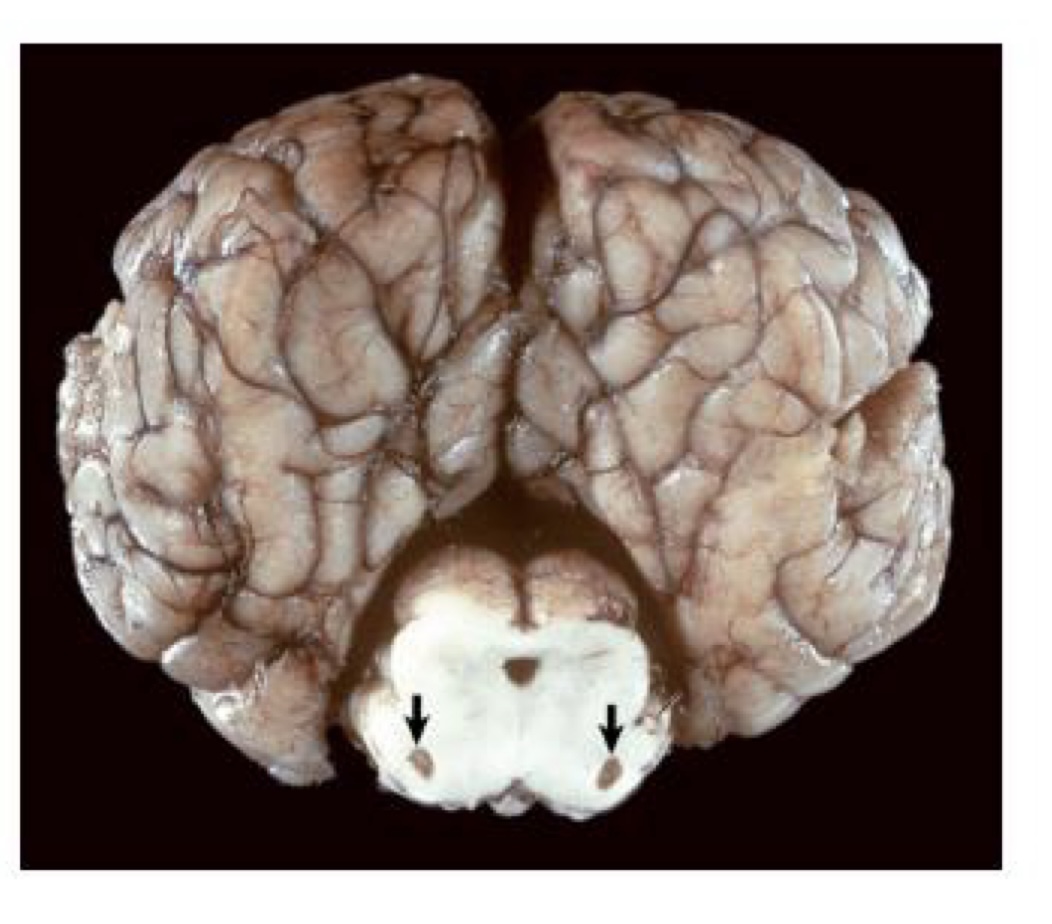

what is this?

medulloblastoma → white to tan, homogenous mass that compresses the cerebellum and brainstem